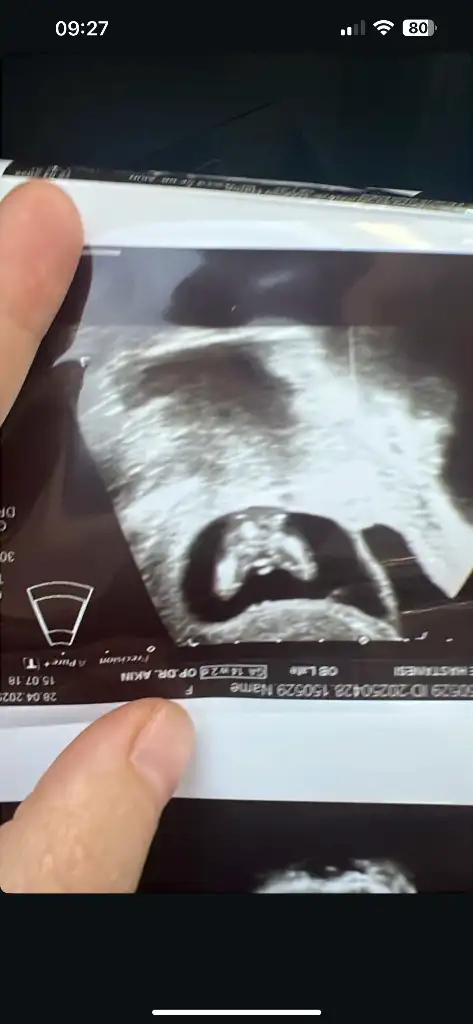

Merhaba ilk önce rabbim hayırlısını ve gönlünüze göre olanı versin inşallah nub teoremine göre sanki kız gibiEki Görüntüle 3580977 cinsiyet tahmini alabilir miyim

Banada bakabilir miisniz görsel olarak yorumlara ekledim :)Merhaba ilk önce rabbim hayırlısını ve gönlünüze göre olanı versin inşallah nub teoremine göre sanki kız gibi

Banada bakabilir miisniz görsel olarak yorumlara ekledim :) ilk görsel 10+4 diğer görseller 6+4 haftalıkken karından ultrasonla bakıldı

Pek anlamıyorum ama kendim için araştırmaya girdim kaç gündür araştırmalarıma göre kız gibi geldi banaBana da tahminde bulunabilir misiniz kızlar 10. Hafta goruntumden

Merhaba nub teoremine gore kiza benzettim ben ama rabbim go lunuze gore versin insallahBana da tahminde bulunabilir misiniz kızlar 10. Hafta goruntumden

Sizce benimki ne olabilir ben erkeğe benzetiyorum ama eminde değilim kız diyenlerde olduMerhaba nub teoremine gore kiza benzettim ben ama rabbim go lunuze gore versin insallah

benimkine de bakın bu nedir iki bacak arası görünüyorVajinal ultrasonla bakıldıysa bebeğiniz kız olabilir